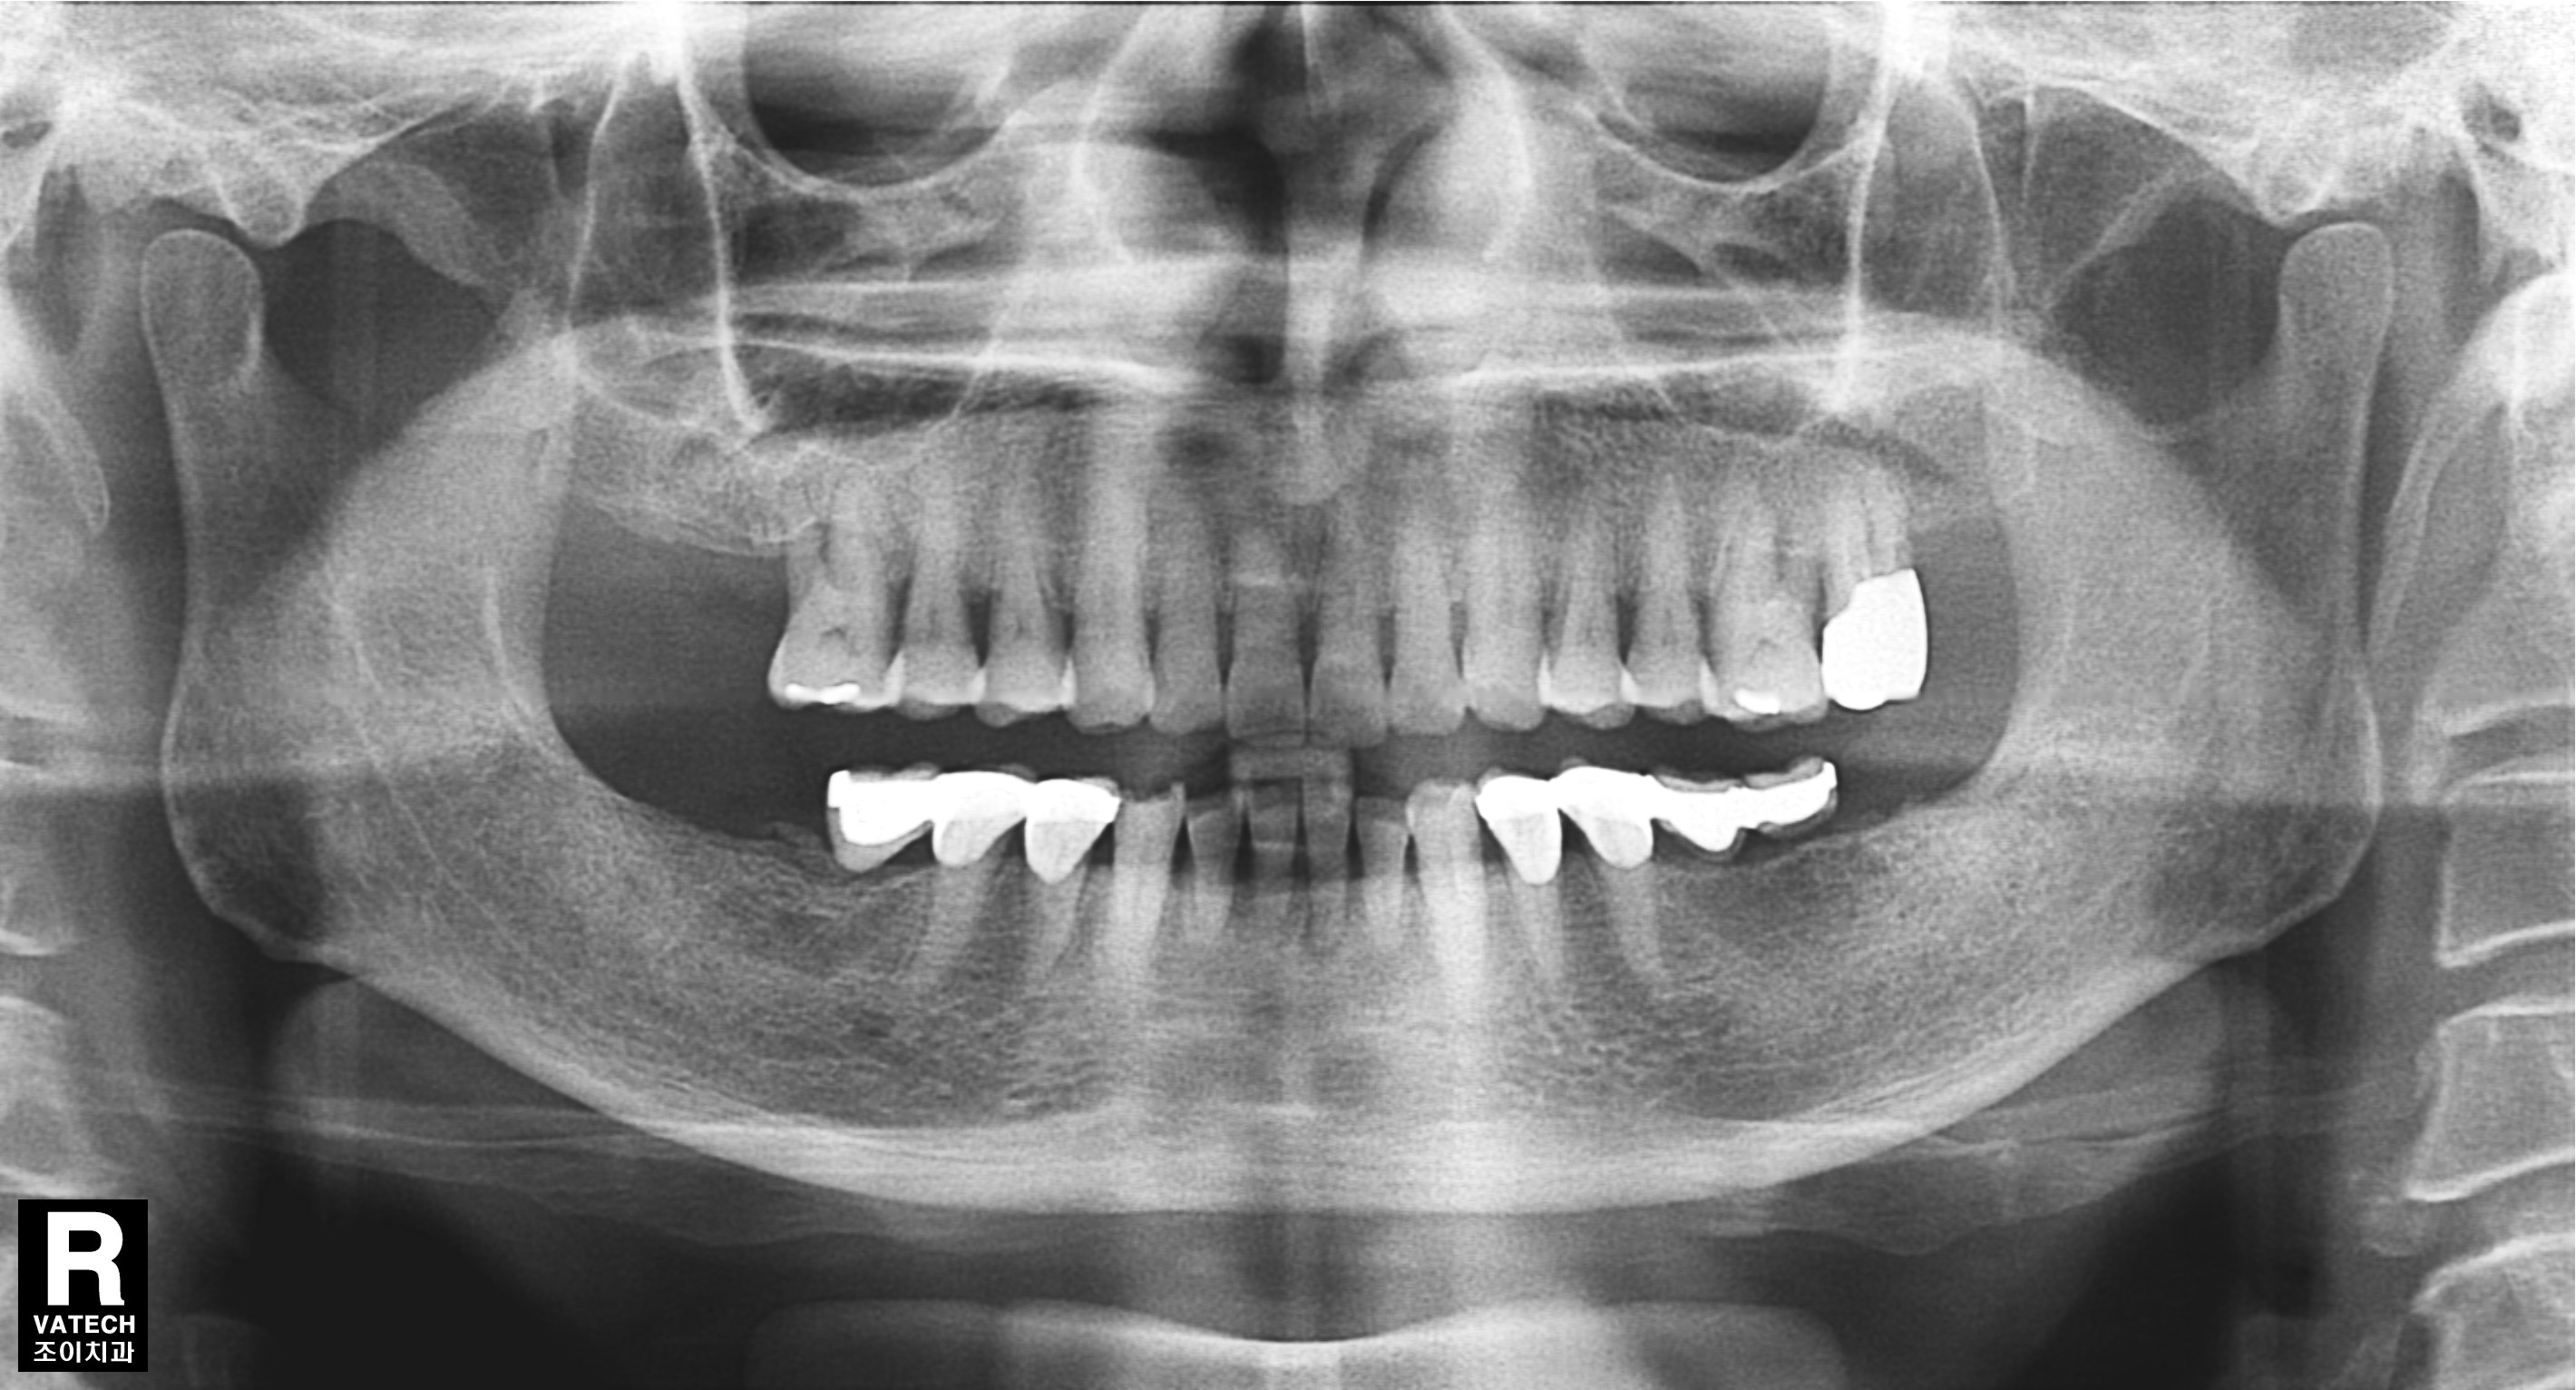

[임플란트] 제목 : 오래된 보철의 수리 및 임플란트

후방연장된 보철은 그 안에서 2차우식이 일어나기 쉽습니다.

문제가 된 보철을 제거하고 재치료한 례입니다.